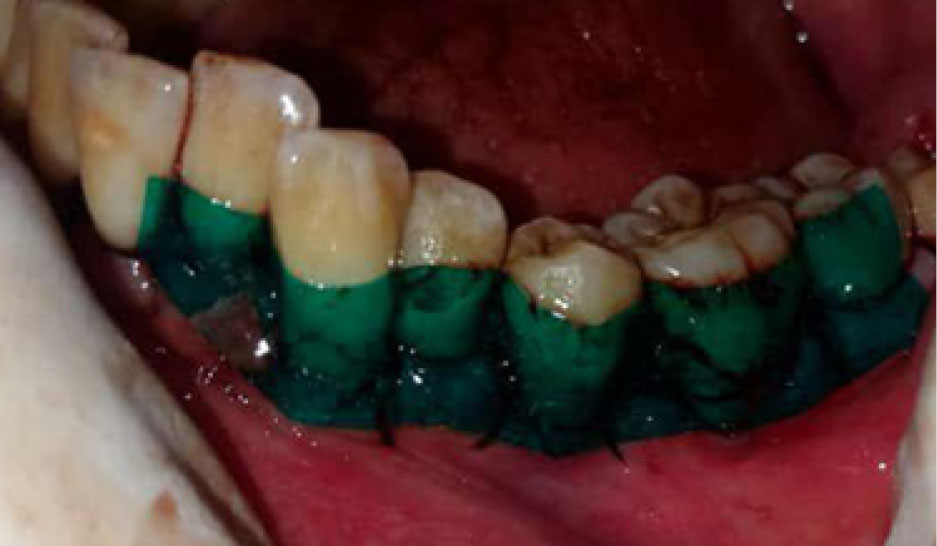

Flap surgery was performed in each quadrant following the standard protocol of site preparation, incision, flap reflection, and thorough debridement. Minimal bone contouring was performed in some cases of both groups, while no case required any bone grafting. Primary closure was achieved using 3-0 silk suture on a 3/8 circle reverse cutting needle. Thereafter, in the control group, Coe-PakTM was placed at the surgical sites (). Equal lengths of base and catalyst paste of this dressing were mixed on a glass slab according to manufacturers’ instructions. It was applied and pushed well into the embrasure spaces using moist gloved hands to mold it to the required contour. It was extended from one tooth mesial to the first suture to one tooth distal to the last suture of the surgical segment, extending from the cervical third of teeth to the mucogingival junction. Diplen LX dressing was placed in the intervention group (). Occlusal clearance over the dressing was also checked. The extent of the dressing was the same as described above with Coe-PakTM. In both cases, patients were given postoperative instructions and advised to rinse with 10 mL of 0.2% chlorhexidine gluconate solution twice daily for one week to control plaque. They were also prescribed ibuprofen tablets (600 mg three times daily for three days). On the 7th day after surgery, the periodontal dressing was removed in two parts (buccal and lingual) using a dental tweezer and a blunt probe. The patients were asked to fill an assessment questionnaire and rate the preferred dressing based on pain and discomfort experienced, taste, appearance, retention, burning sensation, and sensitivity experienced with each type of dressings. Wound healing index (WHI) parameter12was also evaluated at the surgical site on the 7th and 14th days after surgery in both groups.Patient-reported parametersincluded pain assessment based on the verbal rating scale and patient’s preference based on burning sensation, hypersensitivity, appearance, taste, and retention of dressings. This parameter was also evaluated on the 3rd and 7th days after surgery in both groups. Evaluation of wound healing was based on the parameters of tissue color, bleeding in response to palpation, the presence of granulation tissue, and the condition of incision margin. Each of these four parameters was separately assessed on the scale of 1 (very poor) to 5 (excellent), and the total score was finally divided by 4 to achieve the WHI score.

joddd-16-135-g002

Figure 2. Diplen LX Dressing used in control group.